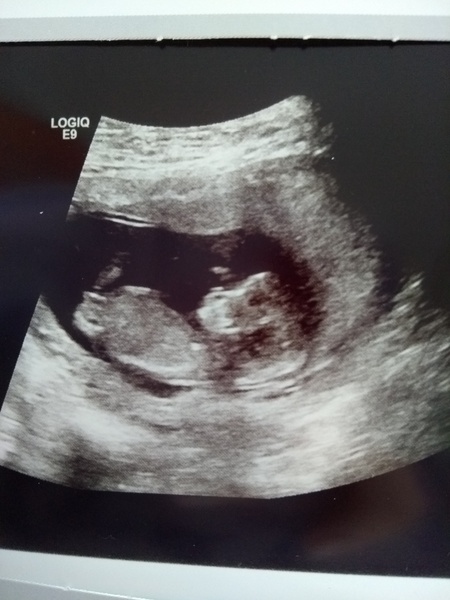

Good news here today too. Celebrated by buying some lovely m&s stretchy trousers! You can make out the little footprint on the scan and it has one of its hands by its face. Really happy and relieved.

Scan today went well. Due date is now the 9/11. Can relax a bit now I hope

Congratulation @moomoo85. Lovely pic!